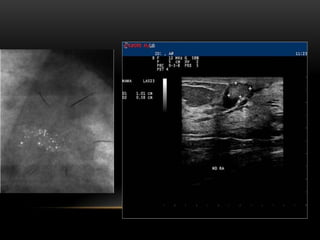

MICROQUISTES

AGRUPADOS

QUISTES

COMPLICADOS